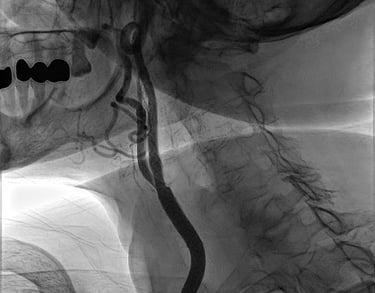

CORONAROGRAFIA

La Coronarografia è l’esame piu’ approfondito per valutare la presenza di restringimenti (“stenosi”) a carico delle arterie coronarie, ovvero delle arterie che nutrono il cuore. Viene effettuata tramite utilizzo di appositi cateteri che vengono inseriti attraverso l'arteria radiale o femorale. Per acquisire le immagini viene utilizzato un liquido chiamato “mezzo di contrasto” che opacizza il lume delle arterie mescolandosi al sangue. Le immagini vengono acquisite da un macchinario che emette una debole radiazione e registra le immagini.